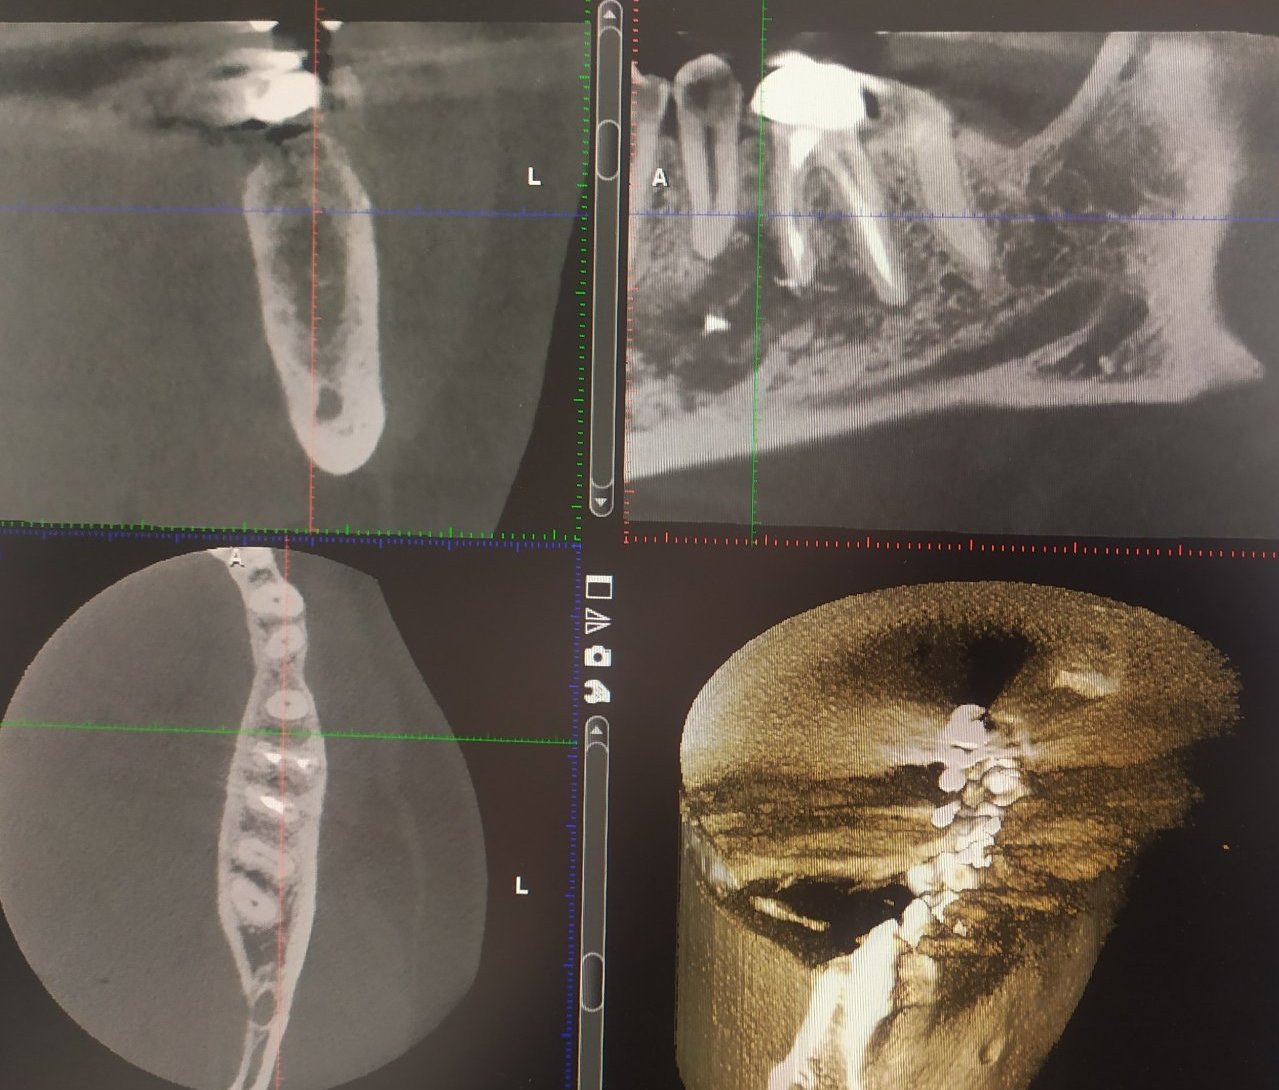

Това са снимки от скенера - преди лечението и след-

Скрит текст: